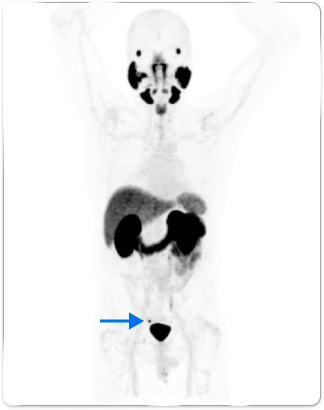

Patient A

Anterior whole body PYLARIFY PET MIP showed uptake in the right peri-rectal lymph node (blue arrow)

In patients with similar profiles, PYLARIFY identified differences in extent of disease, guiding treatment changes

- Treatment change from EBRT to pelvis with additional boost to prostatic fossa, to lesion-specific SBRT

- Post-treatment PSA levels dropped to 0.06 ng/mL